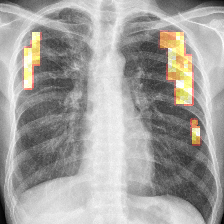

Figure 1: Overview of marginalization: (a) original with annotated mass (red box) before and after marginalization by our method; (b) local comparisons with popular methods (clockwise): original, blurring [9], inpainting (ours), and averaging [29]; (c) ROC curves of the mammography classifier (green curve) vs. healthy pixel inpainting only in healthy/pathological (blue/red curves) structures.

Thus, we computed ROC curves using the classifier on all test samples (i) without any inpainting as reference, and for comparison, randomly sampled inpainting (ii) only in healthy respective (iii) pathological scans over 10 runs (Fig. 1). The clear distance between the ROC curves of the mammography image classifiers without any inpainting, yielding an AUC of 0.89, and with inpainting in pathological regions, resulting in an AUC of 0.86, shows that the classifier is sensitive to changes around pathological regions of the image. Moreover, it is visible that the ROC curves of inpainting in healthy tissues with an AUC of 0.89 follow closely the unaffected classifier’s ROC curve (Fig. 1). The AUC scores for the TBC classifier without and with inpainting in healthy tissue are 0.89 and 0.88 which proves the above mentioned observations. Pathological tissue inpainting was ommitted in this case due to the lack of pixel-wise annotations.